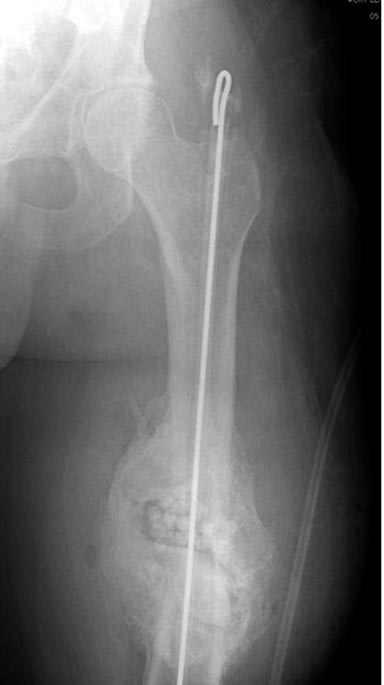

Гвозди с антибиотиком все custom made, т.е. делаются во время операции.

Диаметр зависит от внутреннего диаметра канала. Обычно достаточным

бывает 10 мм, и редко применяется готовые гвозди для армирования

цемента. Трубка в 10 мм для плевральной полости как форма и армирование

2.8 или 3.2 мм guide wire для гвоздей, которая срезается по длине, на

конце делается петля для облегчения удаления.

В представленном случае, из-за большого диаметра первичного гвоздя

(13мм) применили готовый гвоздь в 11 мм, а трубка с внутренним диаметром

16 мм.

Здесь представлены примеры подготовки гвоздя....